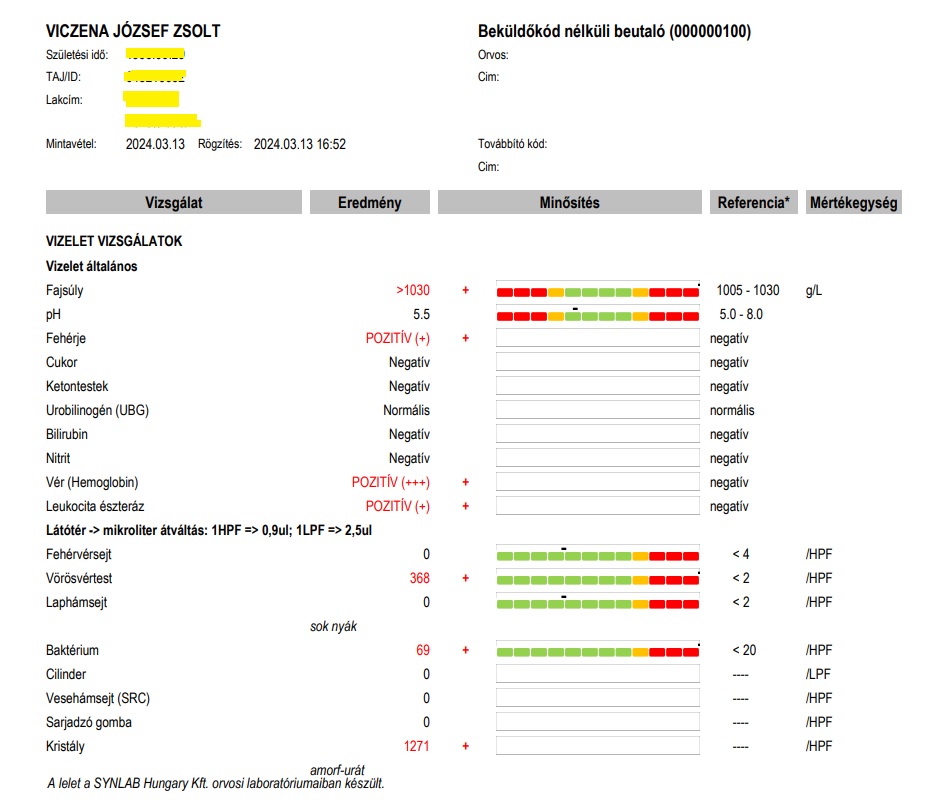

11./ Március 13. Újra Semmelweis Egyetem I. sz. Belgyógyászati és Onkológiai Klinika: Dr Ledó Nóra

A fiam látta, hogy reggel az EESZT-be bejegyezte Ledó Nóra, hogy nincs nefrológiai teendő, a továbbiakban keresse fel háziorvosát, akinél 3-4 havonta csináltasson vizelet és vérvizsgálatot. Mintha a fiamnál minden rendben lett volna! Pedig ekkor már több mint 1 hónapja szenvedett kezeletlenül, nézni alig lehetett: Éjjelente 8-10 vizelet, délelőtt 5-6 hasmenés, 0-24 kétoldali elviselhetetlen vesefájdalom, hőemelkedések, hányinger, gyomortáji fájdalom, nagyon magas pulzus. (Súlyos vesemedence-gyulladás tünetei!) Éppen amikor a fenti sorokat Dr Ledó beírta az EESZT-be és lezártnak tekintette Zsolt esetét, visszatért a vérvizelés!

Rohantunk Budapestre a vizeletmintával, leadni a Semmelweis laborba. Az eredmény sokkoló lett:

A vizeletet Dr Ledó Nóra eredetileg a portára (!) akarta velünk leadatni. Nem tudom, hallott-e már valaki ilyet?! Persze a laborba vittük és megvártuk míg adminisztrálják, hogy biztos ne történjen olyan véletlen, hogy eltűnik. Ezután siettünk magánúton (abszurdum) szívultrahangra, ahol 29 ezer forintot fizettünk ki a cégnek, mert Dr. Ledó azt mondta a komoly baloldali mellkasi-szívtáji és lapockatáji-háti fájdalommal küzdő fiamnak – ami tünetek egyszerre jelentek meg a vérvizeléssel, vesefájdalommal, magas pulzussal – hogy „Nem tudom elintézni, a klinikán 4-5 hetet kell várni egy szív ultrahangra”. Teljesen gúnyt űzött az orvosnő a fiam súlyos állapotából. Ekkor be kellett volna menni az igazgatóhoz, hogy egy SOTE Belklinika hogyan teheti ezt meg akut betegekkel? Talán ha felvette volna a borzalmas állapotú fiamat a kórházba, egy napon belül is megtörténhetett volna TB-finanszírozottan. Visszatérve az eredményre, a vizelet 10 pozitív eltérést mutatott, mivel nehéz lehet az apróbetűket olvasni, az alábbiakban leírva is közlöm:

– 2 keresztes fehérjevizelést

– 3 keresztes vérvizelést

– vörösvértestek zsúfolva/látótér! (egy másik ottani nefrológus azt mondta, 10-15 vvt/látótér értékekkel találkozik a napi gyakorlatban – Zsoltnak 100 és 1000-szerese volt ennek, ismét!)

– fehérvérsejt (genny) 10/látótér (ref. érték: 2) – ezúttal már genny is volt a vizeletben, amit a doktornő gátlástalanul letagadott nekem

– baktériumok sok/látótér

– Calcium-oxalát kristályok sok/látótér.

– Albumin a vizeletben több mint 3-szorosa

– Összfehérje a vizeletben több mint 7-szerese (a vese átengedi a fehérjét!)

– Kreatinin a vizeletben 3-szorosa a normális értékek felső határának.

Visszatérve a mintákra, párhuzamosan leadtunk egy mintát a Synlab-hoz is, kvantifikálja az eredményt ellentétben más leletekkel. Szintén alarm eredmény!